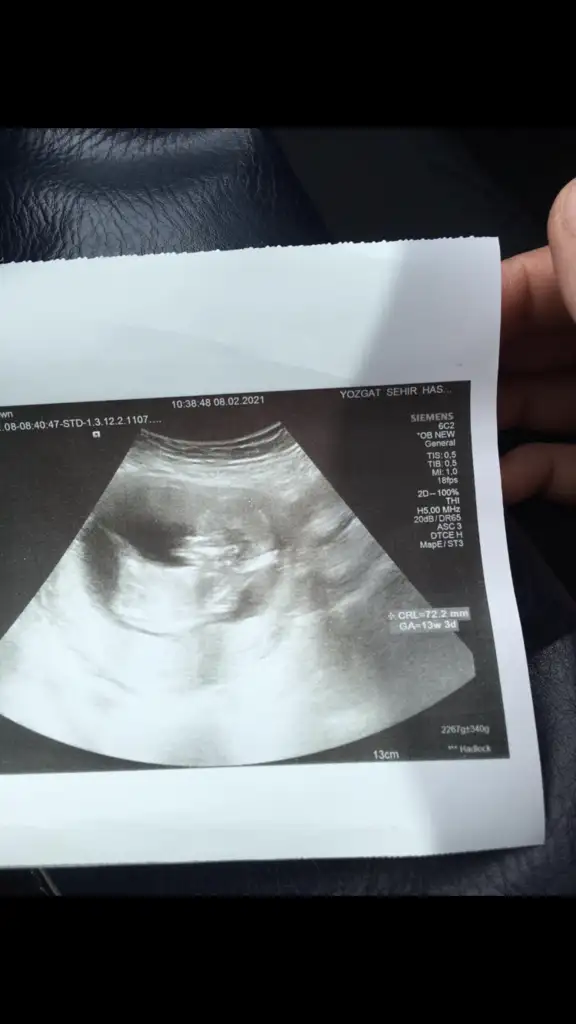

• IMG-20210205-WA0008.webp

IMG-20210205-WA0008.webp

29,3 KB · Görüntüleme: 67

Merhaba lutfen yardimci olurmusunuz 11 hafta 6 gunluk karindan ultrason